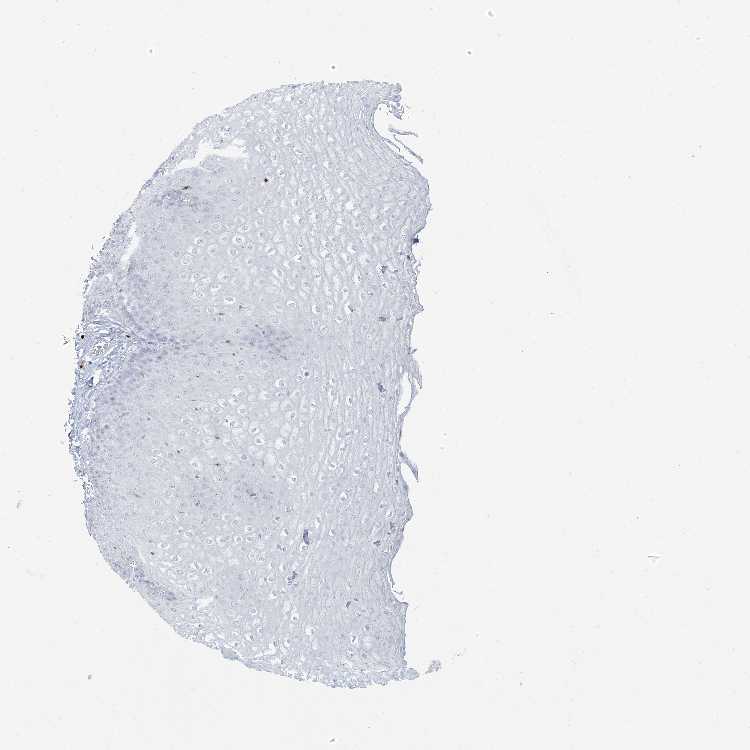

ESOPHAGUS - Antibody stainingi

Antibody staining in the annotated cell types in the current human tissue is reported as not detected, low, medium, or high, based on conventional immunohistochemistry profiling in selected tissues. This score is based on the combination of the staining intensity and fraction of stained cells.

Each image is clickable and will lead to virtual microscopy that enables deeper exploration of all samples and also displays staining intensity scores, fraction scores and subcellular localization as well as patient and tissue information for each sample.

Antibody HPA043151Antibody CAB015400Antibody CAB034021

Squamous epithelial cells Not detectedNot detectedNot detected